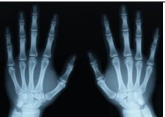

Hình bên là ảnh xương bàn tay được chụp bằng phương pháp → chụp X quang.